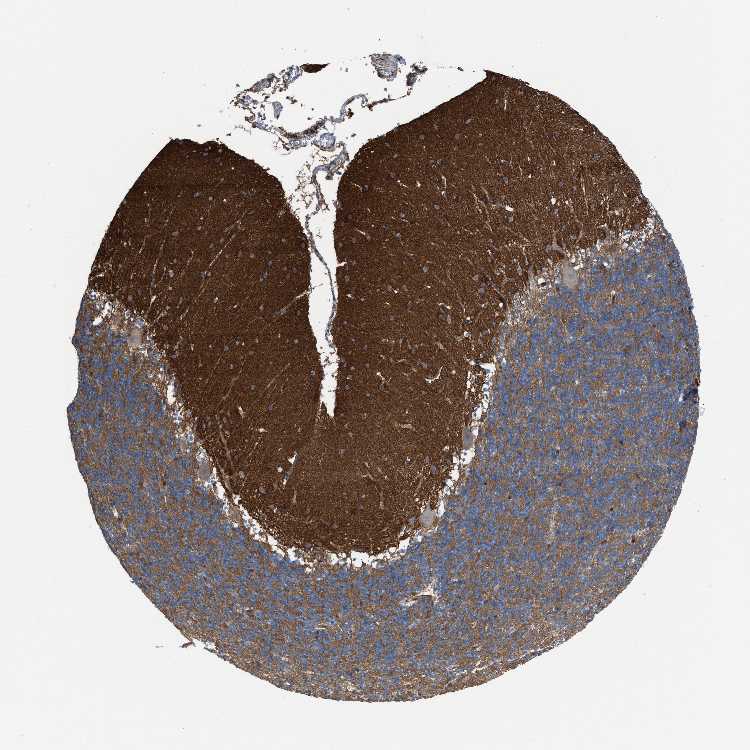

CEREBELLUM - Antibody stainingi

Antibody staining in the annotated cell types in the current human tissue is reported as not detected, low, medium, or high, based on conventional immunohistochemistry profiling in selected tissues. This score is based on the combination of the staining intensity and fraction of stained cells.

Each image is clickable and will lead to virtual microscopy that enables deeper exploration of all samples and also displays staining intensity scores, fraction scores and subcellular localization as well as patient and tissue information for each sample.

Antibody HPA021545Antibody HPA021849

Purkinje cells MediumNot detected

Cells in granular layer MediumMedium

Cells in molecular layer MediumMedium